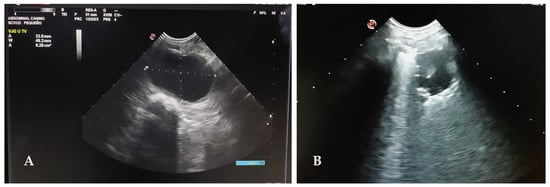

- Lisciandro, G.R. (Ed.) Chapter 11: POCUS: Urinary Bladder. In Point-of-Care Ultrasound Techniques for the Small Animal Practitioner, 2nd ed.; John Wiley & Sons: Hoboken, NJ, USA, 2021; pp. 211–224. [Google Scholar]